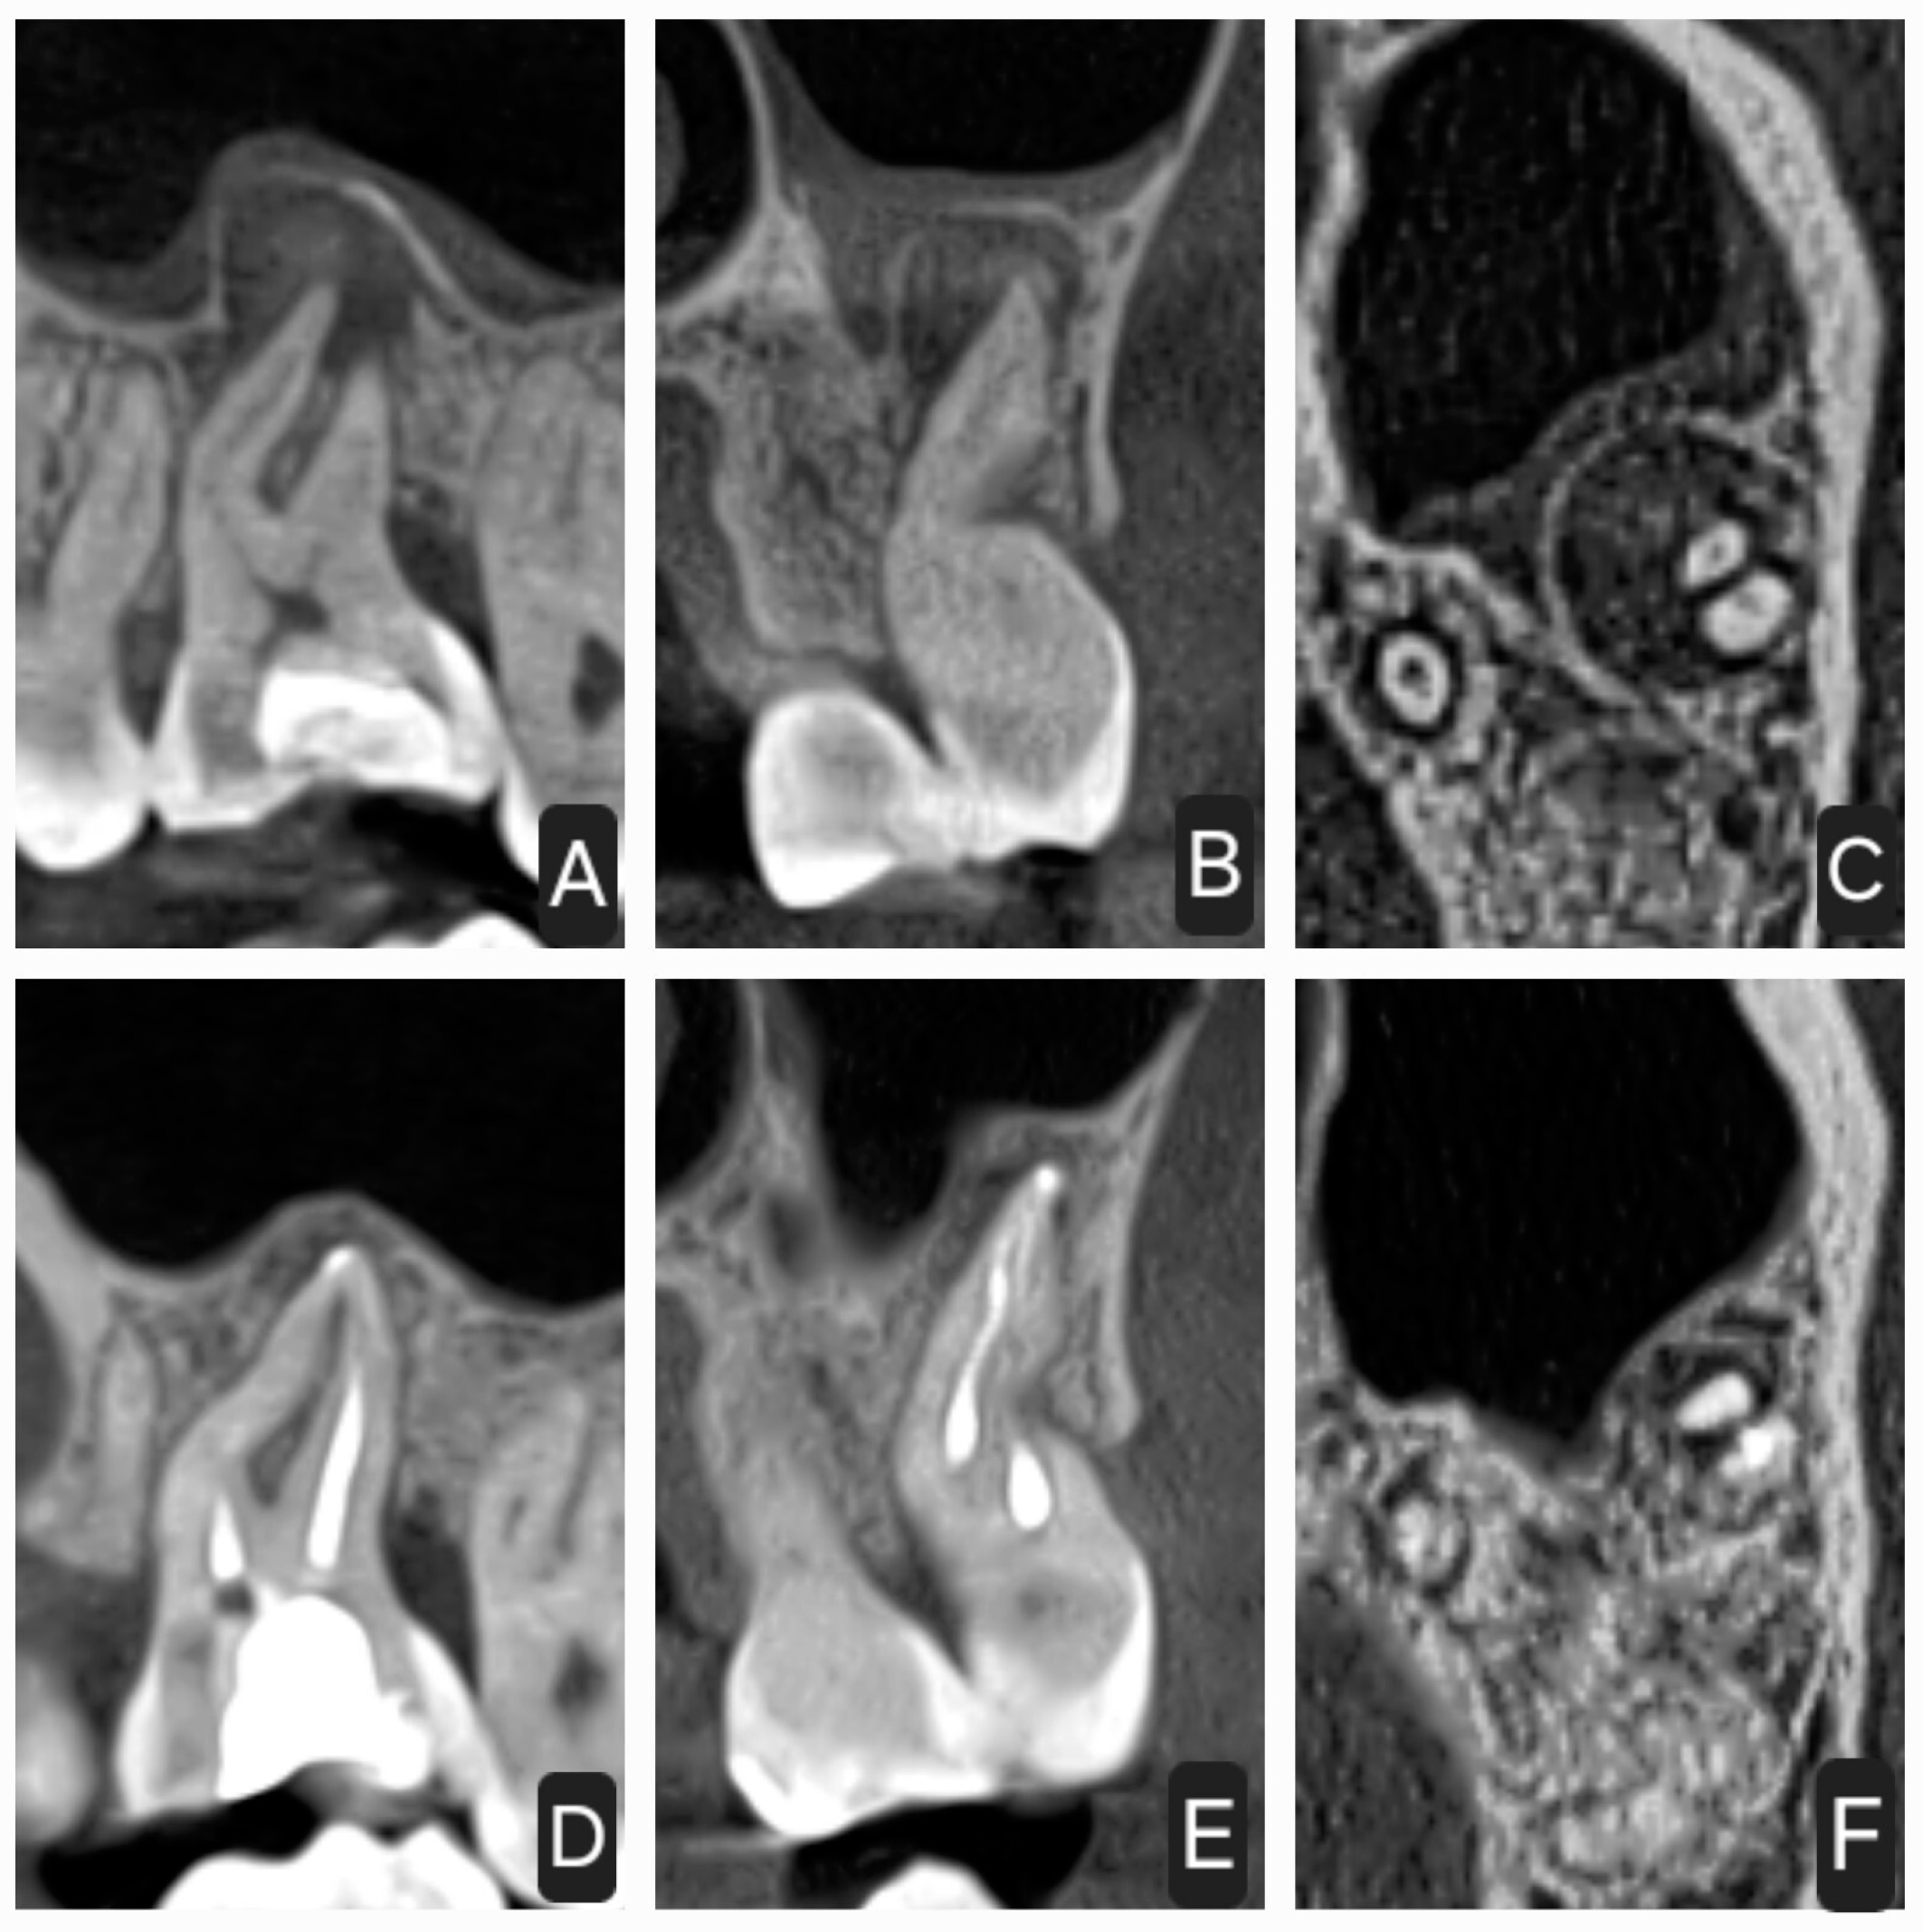

2.1. First Case

2.2. Second Case

2.3. Third Case

2.4. Fourth Case

2.5. Fifth Case